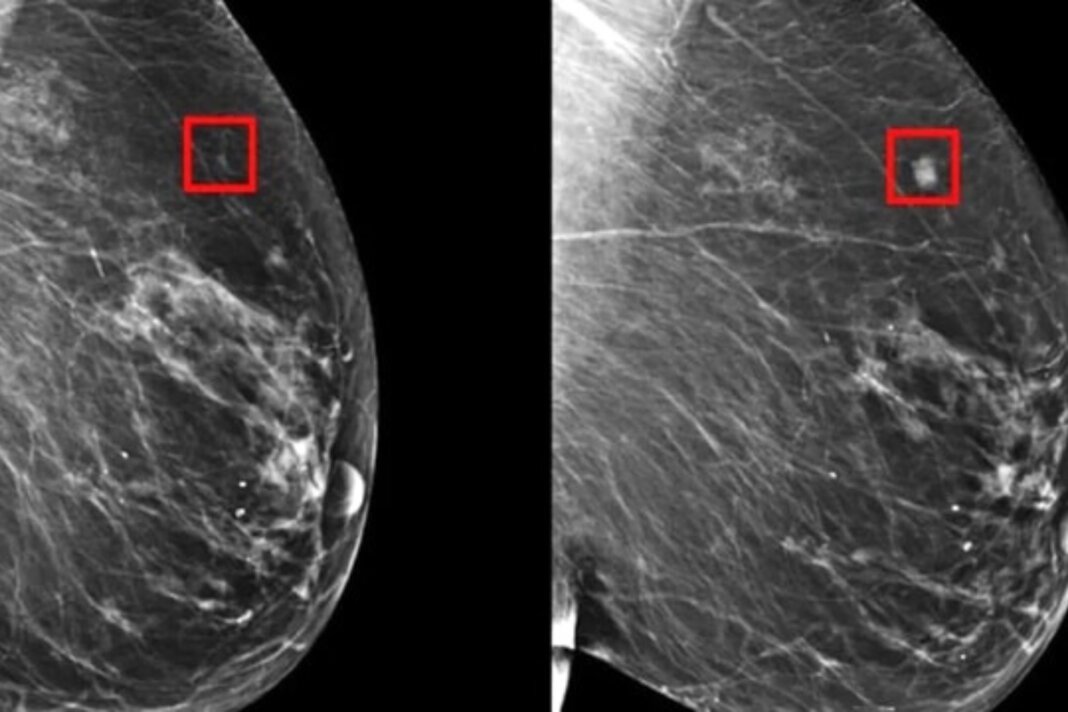

I migliori risultati si hanno quando alla natura umana si affianca la tecnologia: “Nel nostro percorso abbiamo implementato l’intelligenza artificiale. L’Ai ci permette di catturare con anticipo eventuali rischi di tossicità che i nostri trattamenti possono rilasciare. In questo modo, il medico può intervenire tempestivamente ed evitare che un effetto collaterale possa diventare invalidante. I risultati benefici riguardano la paziente e l’intero sistema sanitario nazionale perché migliora la gestione complessiva del percorso di cura che affrontiamo ogni giorno”, conclude Garbognin.

Sul punto: L’intelligenza artificiale può rilevare il cancro al seno con cinque anni di anticipo